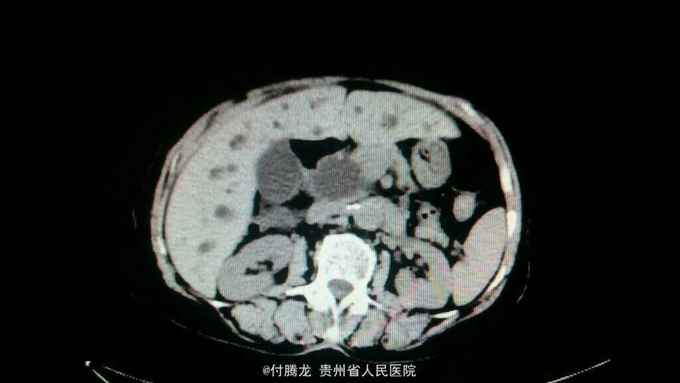

全身黄染伴乏力2月 病史:患者2月前无明显诱因下出现乏力,无恶心呕吐,畏寒发热等,后逐渐发现全身皮肤黄染。遂至当地医院检查。腹部ct提示胆总管下段狭窄,不排除炎性狭窄。胆红素200+。为进一步治疗来我院。

查体:全身皮肤及巩膜重度黄染,上腹轻压痛。 辅助检查:胆红素234,直接胆红素106,间接胆红素128。ALT60,AST88。肿瘤指标199及AFP正常。腹部ct提示胆总管肠内段高密度结节,不排除结石。超声內镜提示胆总管下段梗阻,考虑壶腹部肿瘤。MRCP提示十二指肠壁内段梗阻。